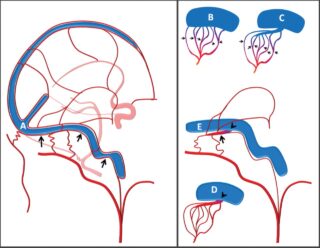

Certain patients can develop symptoms due to bleeding into the brain causing a hemorrhagic type of stroke. Patients at risk are those who have an AVF that drains blood directly into veins of the brain — a condition called cortical venous drainage, or CVD (Figure_picture). Symptoms suggestive of brain hemorrhage include sudden-onset headache, nausea, vomiting, weakness or numbness on one side of the body, difficulties with making or understanding speech, loss of vision, double vision and balance difficulties. If you experience any of these symptoms, seek medical help immediately. Brain hemorrhage is a serious form of stroke that can cause serious brain injury and even death, although many patients make good long-term recoveries.

Patients whose AVF drains blood into veins of the brain (CVD) can also develop seizures, memory loss, and symptoms similar to a stroke, including weakness/numbness on one side of the body, difficulties in speaking or understanding speech, loss of vision, double vision and balance difficulties.